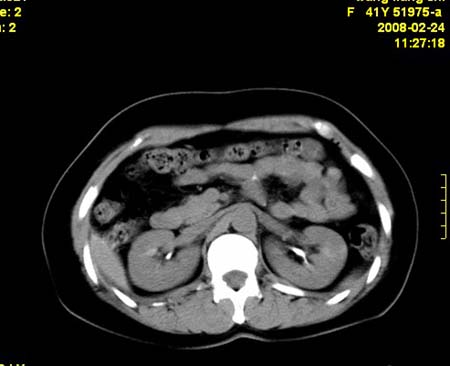

以下是引用dyqct在2009-8-23 16:17:00的发言:[br]考虑:1、造影剂进入腹腔、结肠旁沟、肝周;[br] 2、子宫明显增大(腺肌增生症?);[br] 3、膀胱显影是由于造影剂吸收后经肾分泌进入膀胱的;[br] 4、建议mri检查子宫。